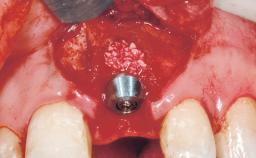

Bone Augmentation Horizontal|Staged

Augmentation Materials Autogenous chips|Membrane

Soft Tissue Grafting Simultaneous

Bone Volume Deficient horizontally, requiring prior grafting